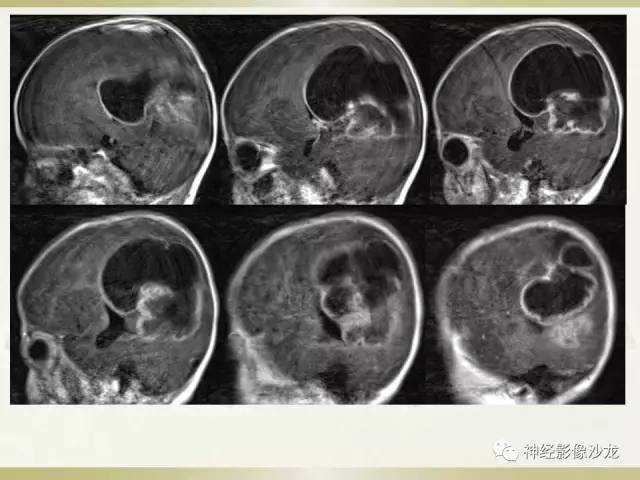

【病例】幕上脑实质内室管膜瘤1例CT及MR影像讨论

囊实性占位,有钙化,实性成分明显强化

箭头标注的地方是左侧脑室后角吧?

这里应该是侧脑室后角

侧脑室三角区受压

儿童,侧脑室三角区旁、囊变、钙化、出血,下次见到首先考虑啊